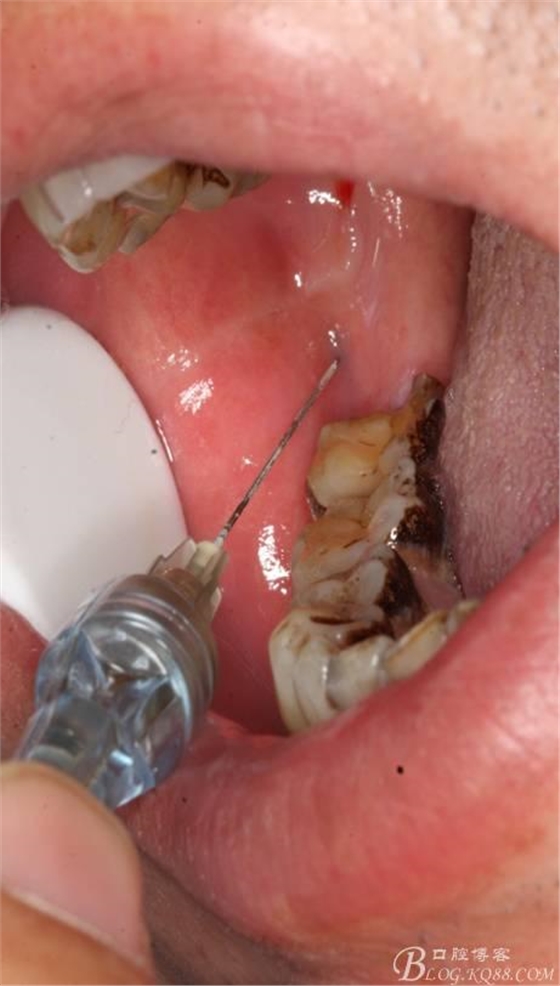

1.麻醉

2.切開翻瓣